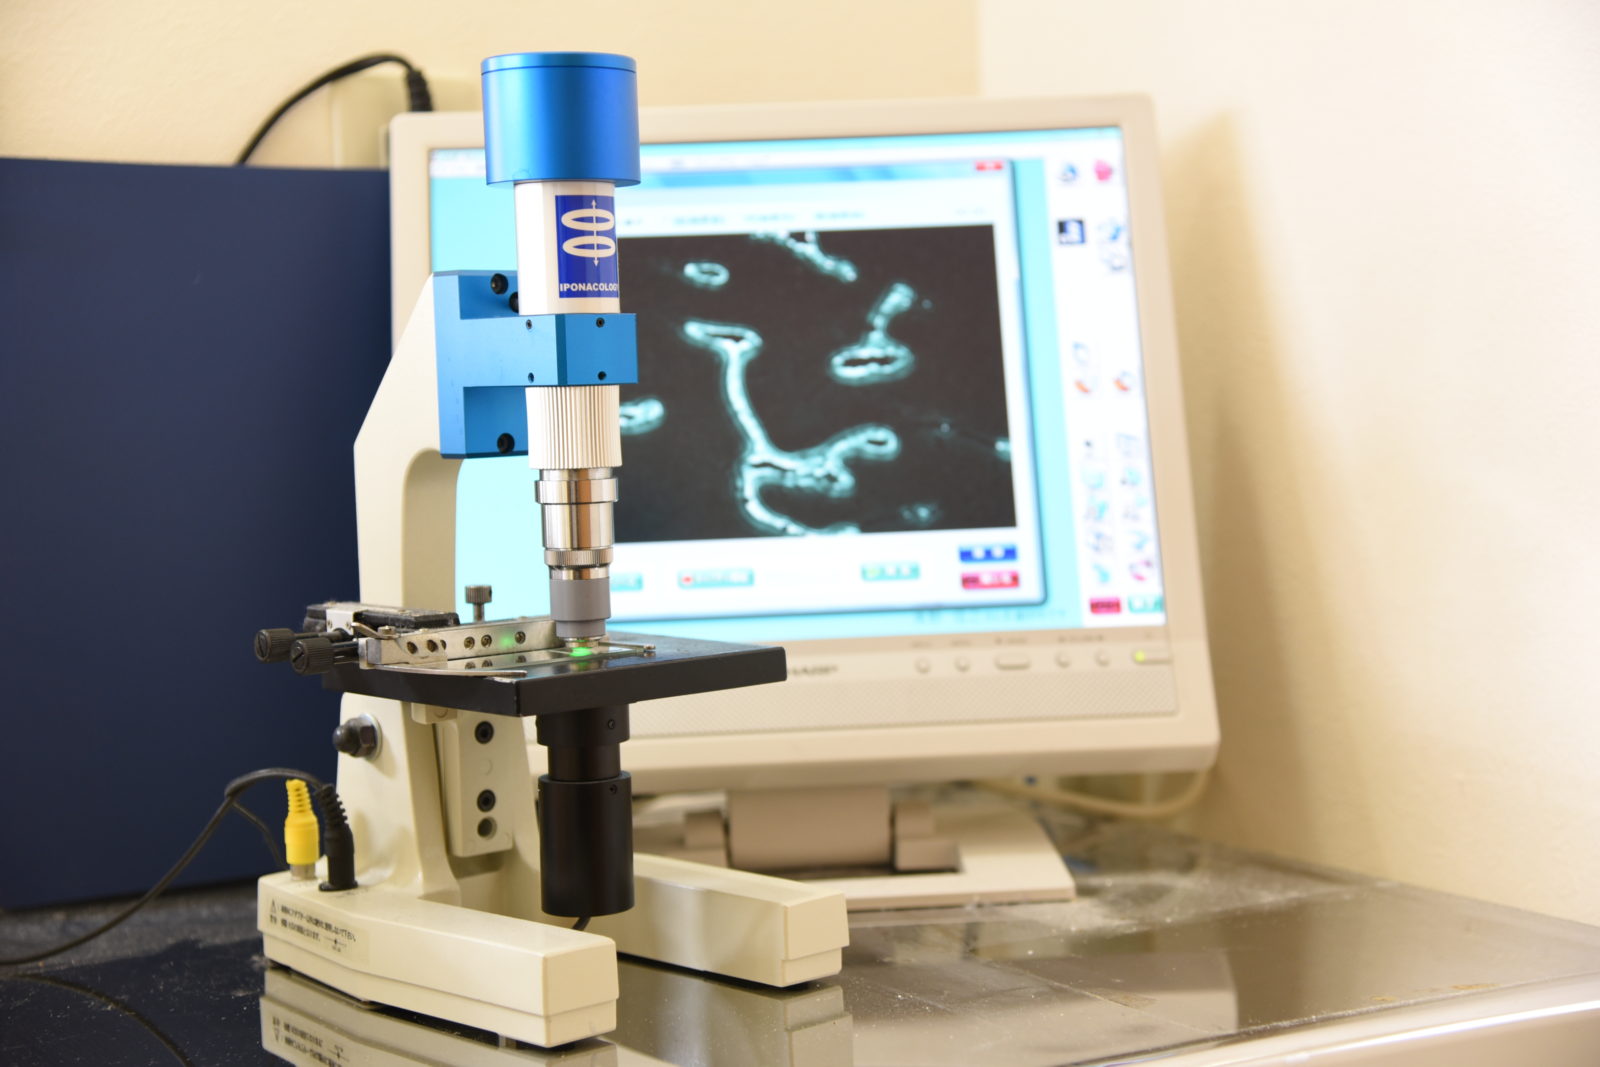

「位相差顕微鏡」は細菌を生きた状態で詳細に観察することができる機器です。治療前の初期診断から治療中の進行具合の確認、さらには治療後の状態観察に至るまで、細菌の微細な変化をリアルタイムで捉えることができます。